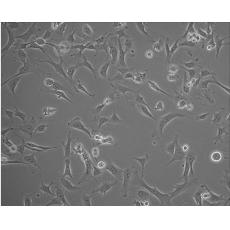

產品名稱 RM-1(RM1)

中文名稱 小鼠前列腺癌細胞

組織來源 前列腺癌;C57BL/6

細胞種屬 mus musculus, mouse

生長特性 adherent

培養基 RPMI-1640+10% FBS+1% P/S

形態特征 epithelial

傳代方法 1:2-1:4